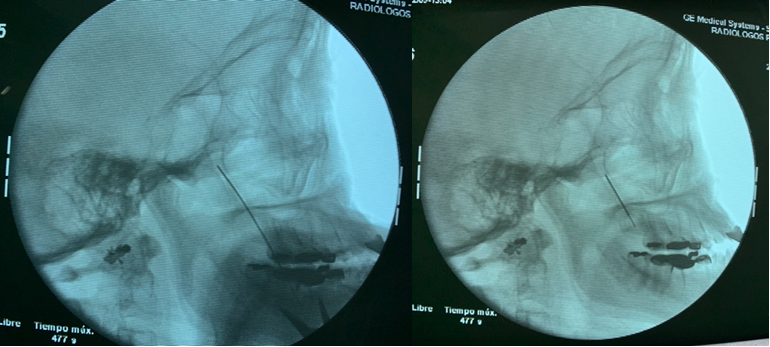

SPG blockade was proposed as a therapeutic option, with prior informed consent. In the operating room and placed in the supine position, the face was prepared and covered in a sterile manner. Superficial sedation was used under standard ASA monitoring. With the head in a neutral position to expose the infracygomatic region on the affected side, fluoroscopy was used to navigate the pterygopalatine ganglion with a 20G (90mm) needle. First, the needle is directed medially in coaxial view until it passes the zygomatic arch (very superficial). Then, is slightly redirected cephalad into the pterygopalatine fossa under intermittent fluoroscopy (Figure 1). In a posteroanterior (PA) view, the needle should be on the lateral wall of the nostril at the level of the middle turbinate (Figure 2).

Figure 2 Posteroanterior view. Needle in the pterygopalatine fossa, just lateral to the nasal wall at the level of the middle turbinate.